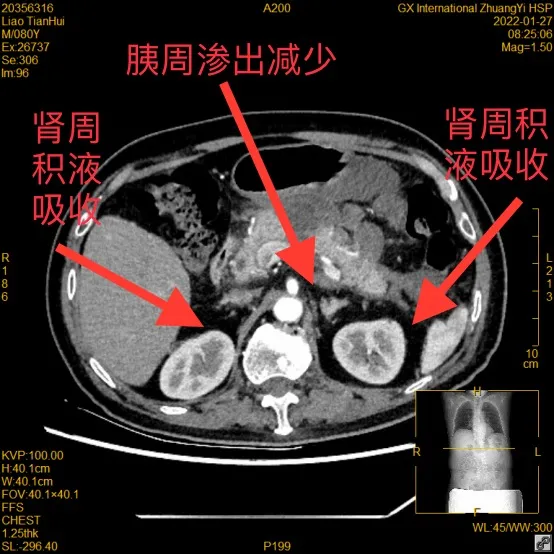

CT检查发现,廖爷爷胰腺周围大量渗出,双侧肾周积液,被确诊为重症急性胰腺炎

最新的CT检查显示,廖爷爷的胰腺渗出减少,双侧肾周积液已被身体吸收,病情稳定